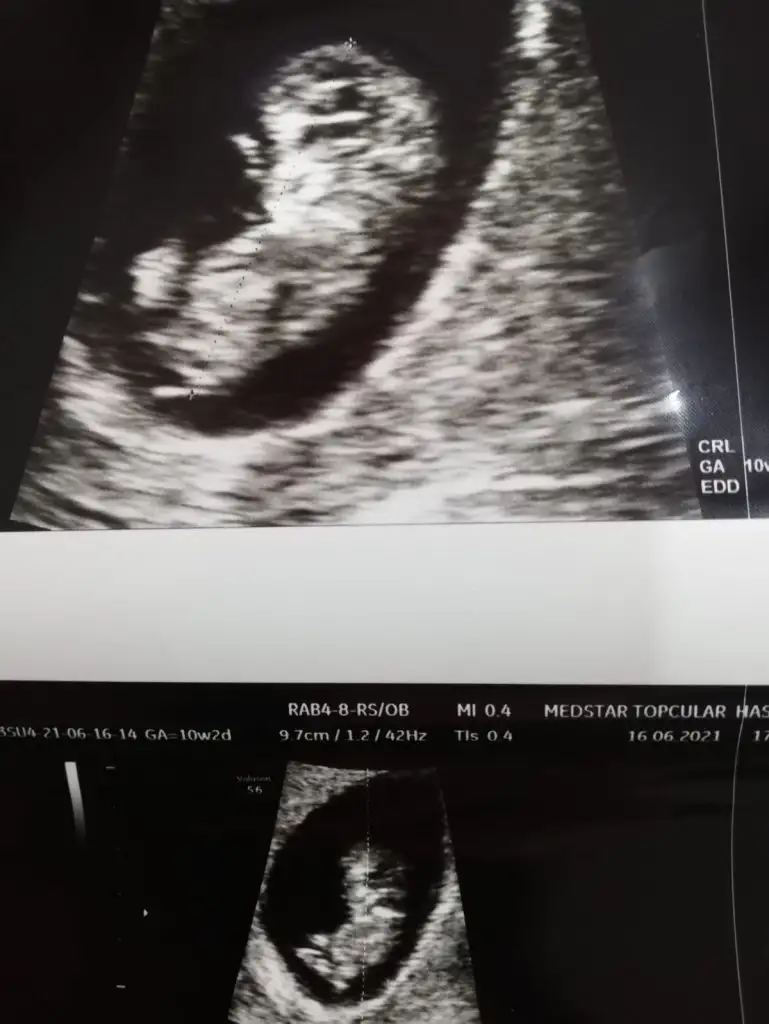

Bana da yorum yapabilir misiniz karından ultrason 9+5

Eklentiler

• 809CD19E-601B-4EF1-BE3B-1C73FB544D78.webp

809CD19E-601B-4EF1-BE3B-1C73FB544D78.webp

20,6 KB · Görüntüleme: 78